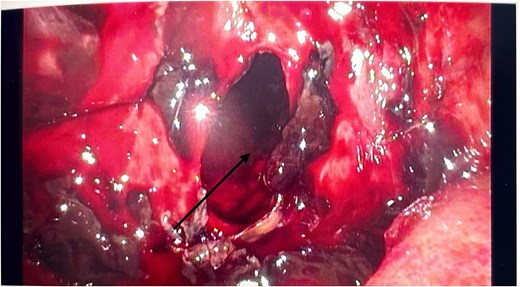

He had an emergency diagnostic laparoscopy. The intraoperative findings included four quadrant haemoperitoneum, ileus involving the stomach, small and large bowels, pelvic floor peritoneal nodules, and a cavity in the retro-colic posterior peritoneum over the pancreas extending into the pancreatic parenchyma with oozing of blood, as shown in Fig. 3.

Intraoperative laparoscopic picture showing a haemorrhagic cavity in the retroperitoneum extending into the pancreas (black arrow).